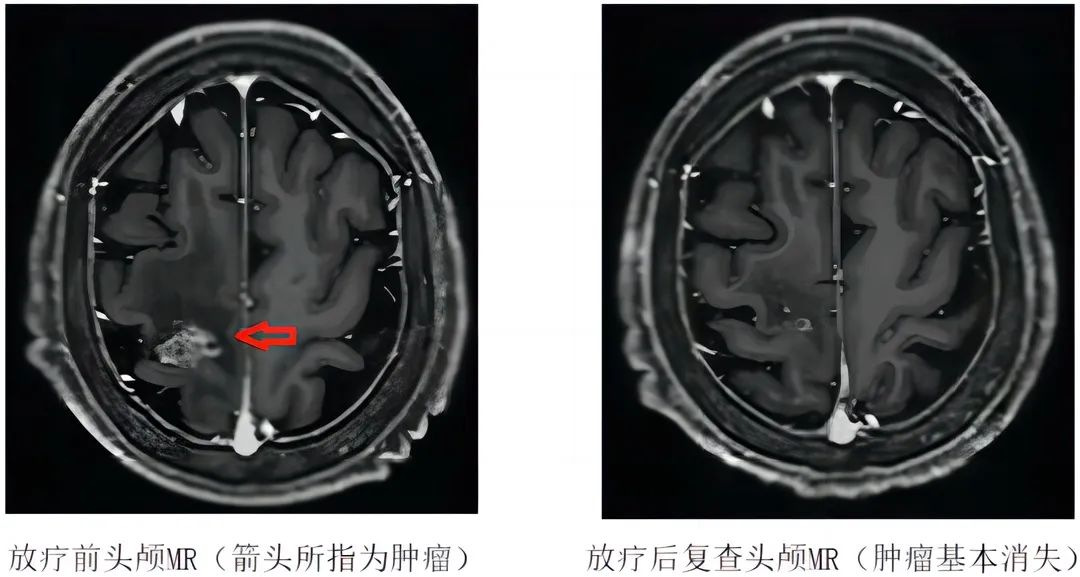

患者于5月12日开始进行脑转移瘤的立体定向放疗(24Gy,共3次,1周内完成)。患者放疗过程顺利,放疗结束后头晕头痛以及右侧肢体乏力的症状明显好转。6月15日(放疗后1个月)患者复查头颅MR见脑转移瘤明显缩小,基本消失。

该患者是我院肿瘤科开展的首例脑转移瘤立体定向放射治疗,根据复查的结果来看,该患者的脑转移瘤基本消失,立体定向放疗的效果显著。立体定向放疗技术对脑转移瘤的治疗效果已得到国内外肿瘤学界的广泛认同。在某些情况下,立体定向放疗可取得与手术切除同等甚至是更优的疗效,在马海清主任及谭佩欣博士带领下实现脑转移瘤无手术也能“切”掉肿瘤的惊奇效果。